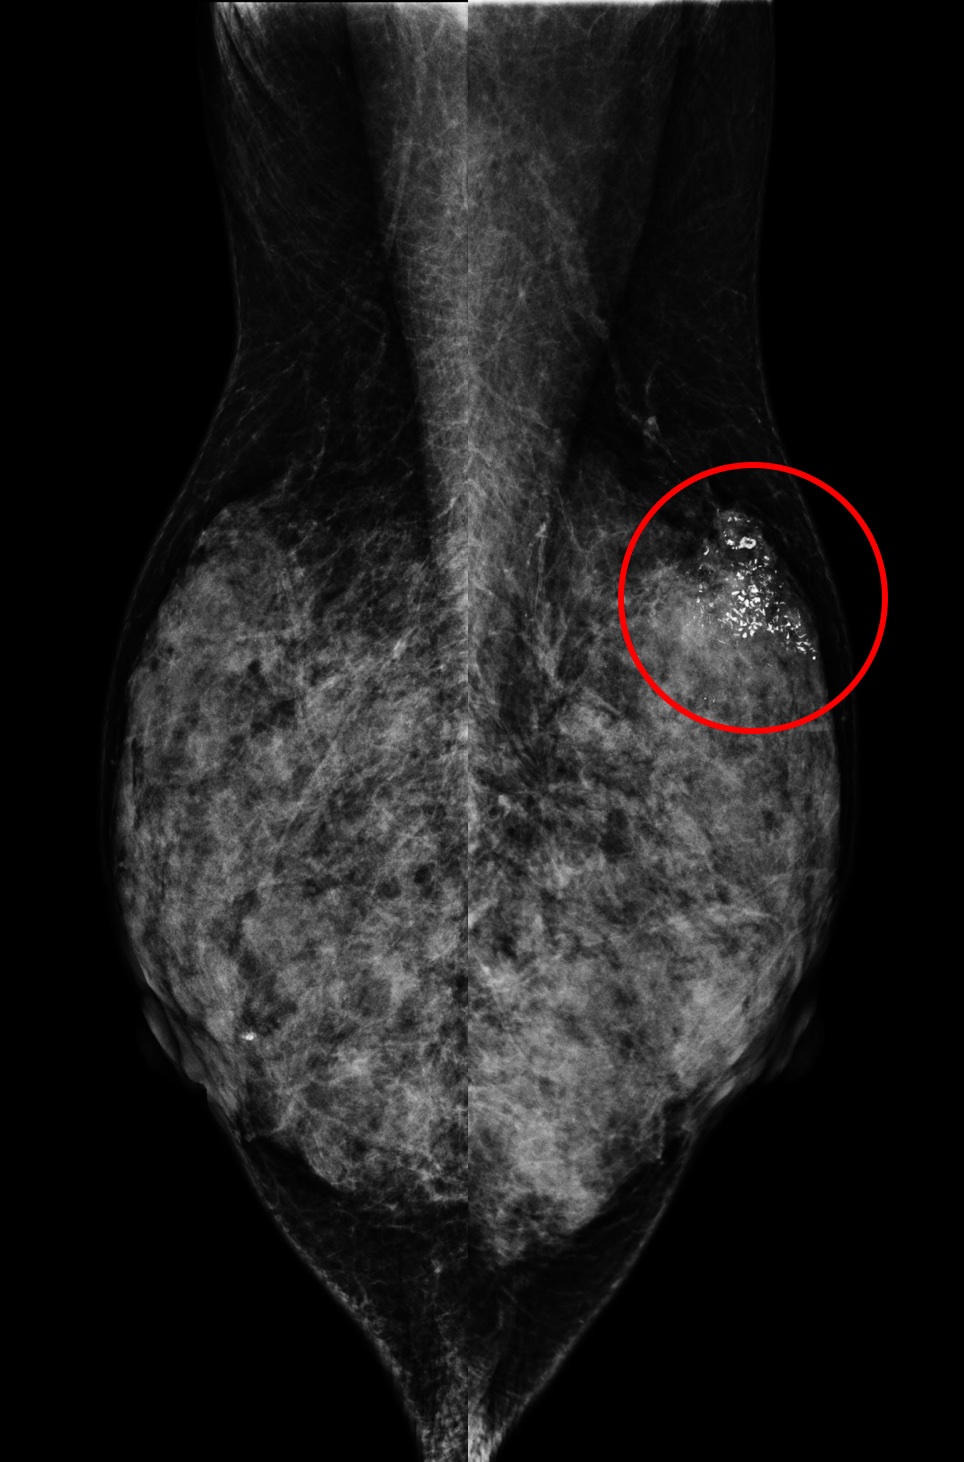

乳房X光攝影

(A) 61歲女性於國健署「乳房攝影篩檢」發現:左乳上方有一不尋常的群聚鈣化點、經手術證實為乳房原位癌,後續恢復良好。

另一名55歲女性於國健署「乳房攝影篩檢」發現:左乳下方有一局部腫塊合併組織變形,經切片證實為早期乳房侵襲癌。